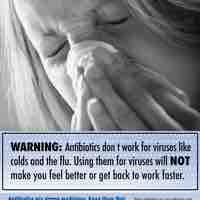

Antibiotic misuse is one factor responsible for the emergence of antimicrobial resistant bacterial strains.

Antimicrobial resistance is a major public health and economic burden on patients, affected communities, and healthcare providers.